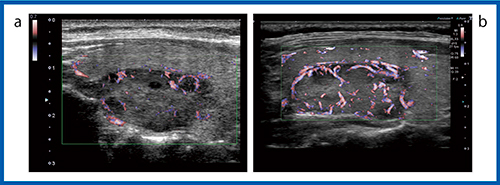

より低速な血流を描出できるSMIでは,装置の性能が向上することで血管の描出能の違いがより明確にわかる。図8は,color-coded SMI(cSMI)でカラー表示された血流の画像だが,Aplio i800(b)では通常の血流に加えて,腫瘍の内部まで入り込むような微細な血管の様子まで確認することができる。また,血流信号をモノクロで表示したmonochrome SMI(mSMI,図9)の場合,Aplio i800(b)では濾胞構造を示す腫瘍の周囲の血管構造まで確認できるほど低流速の血流が描出されている。

濾胞性腫瘍の血管構築は,良性では類円形の血管走行できれいな濾胞を描いているが,癌腫ではイレギュラーに網目状に発達した構造を示す。癌腫は進行するにしたがって主要血管網の中心を貫通する血管が認められ,カラードプラにて悪性を疑う濾胞内部の拍動性の血流と類似する。図9 bのAplio i800のmSMIの画像は,甲状腺濾胞の周囲を囲む類円形状の血流を描出しているとも考えられる。さらに高精細な血流の描出が可能になれば,SMIによって癌腫の複雑な網目状の血管構造が描出できることが期待される(図10)。

図8 cSMIによる充実性腫瘍の描出能の比較(12MHz)

a:Aplio 500 b:Aplio i800